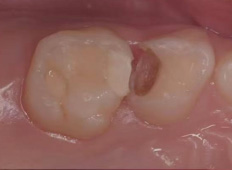

龋齿充填后注意事项

1、树脂充填后即可正常刷牙并可使用患牙咀嚼;

2、如龋坏较深,应暂时避免使用患牙咀嚼硬物,避免对牙髓进一步刺激;

3、龋齿充填后如出现咬合疼痛的情况需及时复诊,调整咬合;

4、龋齿充填后如出现敏感症状,可暂时观察。如不适感长期不能好转甚至加重,出现冷热刺激疼痛或夜间疼痛等情况,应及时就诊;

5、上下前牙充填后充填体较易脱落,应尽量避免啃咬硬物,如果充填体脱落应及时复诊重新充填;

6、后牙龋坏缺损较大或龋坏位置不容易充填固位,患牙充填体反复脱落,建议行预成冠修复;

7、龋齿充填后应保持良好的口腔卫生习惯, 3-6个月定期复查。